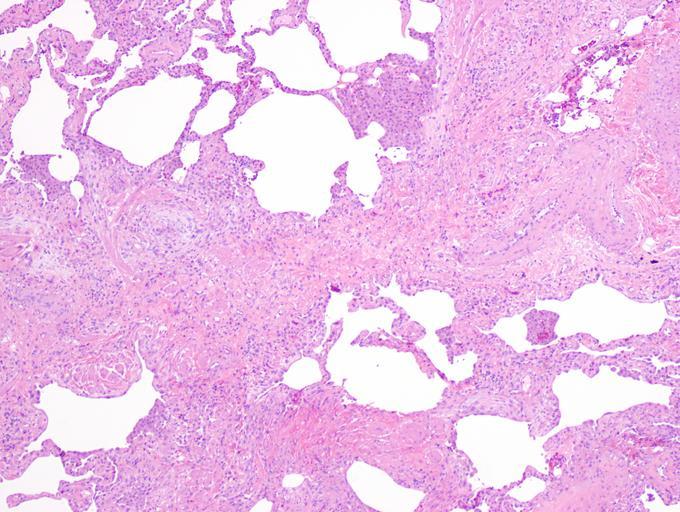

| Keywords: UIPlungbiopsy.jpg en Appearance of usual interstitial pneumonia UIP in a surgical lung biopsy at low magnification The tissue is stained with hematoxylin purple dye and eosin pink dye to make it visible The pink areas in this picture represent lung fibrosis Note the patchwork quilt-like pattern of the fibrosis own Mutleysmith 2009-11-29 Histopathology of the usual interstitial pneumonia Biopsy | ||||